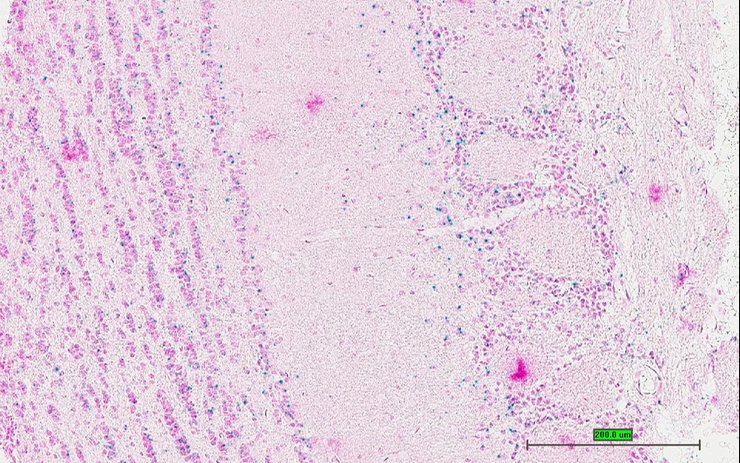

TS28: spinal cord Present UC Davis_1870111

TS28: spinal cord Present UC Davis_1870179

Specimen UC Davis_1870180: postnatal adult; Atf6btm1.1(KOMP)Vlcg/Atf6b+ (more )

Structure Level Pattern Image Note

TS28: spinal cord Present UC Davis_1870180

Specimen UC Davis_1870181: postnatal adult; Atf6btm1.1(KOMP)Vlcg/Atf6b+ (more )

TS28: spinal cord Present UC Davis_1870181